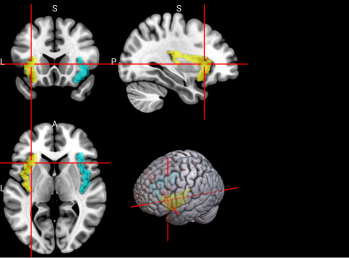

7,8

L & R Inferior frontal gyrus, opercular part

(IFGoperc)

The left inferior frontal gyrus is involved in many cognitive functions including language, executive functioning, social cognition, and inhibition of inappropriate motor responses [61].

/word/media/image10.png/word/media/image10.png